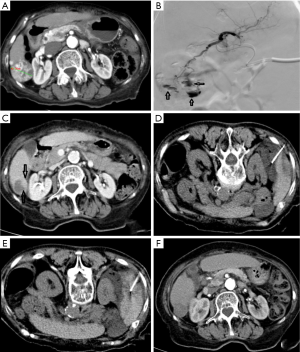

The DEB-TACE procedure for all patients was performed under digital subtraction angiography (DSA) in the interventional operating room of two centers. The procedure was performed by a deputy chief physician or an attending physician with more than 10 years of experience under the guidance of a chief physician. All 92 patients were treatment-naïve and received DEB-TACE for the first time. (I) Local anesthesia was obtained with 1% lidocaine. After femoral artery puncture under local anesthesia, the guide wire and catheter were inserted using the Seldinger technique. (II) After a pigtail angiographic catheter (Cook, USA) was placed for abdominal aortography, a Yashiro catheter (Terumo, Japan) was introduced into the celiac artery and superior mesenteric artery for angiography, so as to identify the site, number, and target vessels of tumors. (III) Callispheres DEBs were loaded with pirarubicin 50 mg (Shenzhen Main Luck Pharmaceuticals, Shenzhen, China). More specifically, a vial of Callispheres DEBs was drawn with a 20 mL syringe and left at room temperature for 5 minutes before the supernatants were discarded. Then, 5 mL of pirarubicin solution was added and let stand for 30 minutes, during which the mixture was gently shaken every 5 minutes. After 30 minutes, 12 mL of non-ionic contrast agent and 3 mL of water for injection were added. Then, the syringe was connected to a T-tube and a 3 mL syringe. (IV) Superselective arterial catheterization into the tumor-feeding vessel was performed using a microcatheter (Progreat; Terumo, Tokyo, Japan), during which any injury to the gallbladder artery, right gastric artery, and non-targeted blood vessels should be avoided. (V) The microcatheter was connected into a T-tube. A 3 mL syringe was used to draw 3 mL of the mixture of DEBs and contrast agent, which was slowly injected into the microcatheter at a rate of 1 mL/min. Meanwhile, fluoroscopy was used to monitor the flow and distribution of the mixture. The microcatheter was intermittently and slowly rinsed with normal saline. (VI) A subjective angiographic chemoembolization endpoint (SACE) level III (9) was used as the embolization endpoint; that is, the tumor stain diminished and the tumor feeding vessels decreased. If unstable VL was found, DEBs and/or blank microspheres (large particle size) and gelatin sponge were used for embolization until the SACE IV level (i.e., both tumor stain and tumor feeding vessels disappeared) was reached (Figure 1). (VII) After reaching the embolization endpoint, a second angiography was performed after waiting 5 minutes. If the embolization endpoint was found to be degraded, further embolization sessions were performed until the embolization endpoint reached a steady state. (VIII) If the embolization endpoint was still not reached after one vial of DEBs was used up, additional embolization sessions with 300–500 µm of blank microspheres were performed until the endpoint was reached. Embolization of the main tumor feeding artery with a gelatin sponge was not performed in patients without unstable VL.

Definition, classification, and statistical methods of VL

The VL was defined as a localized pooling of contrast agent within the tumor in any step of embolization, which persists in the venous phase of angiography, in different forms of lumps or patches. It can be focal, with clear boundary, and is quite different from tumor stain. VL can occur at different stages of embolization, and its shape and size can vary with the injection of DEBs (10-13). In our current study, VLs were divided into two types according to their morphological enlargement and adjacent position: stable and unstable. Stable VLs had no morphological or size changes after multiple angiography scans and were not treated. In contrast, the unstable VLs gradually increased in size on angiographic scans or they were more adjacent to the liver surface; thus, DEBs or large particle-sized microspheres and gelatin sponge (1,000–1,400 µm) were applied for embolization until the VL disappeared and the main tumor-feeding artery was occluded. The embolization endpoint was SACE level IV.

All the 92 HCC patients were treatment-naïve, and DEB-TACE was applied in the first interventional therapy. The success rate was 98.9%. Among them, 43 patients had a single nodule while 49 (64%) had multiple nodules. A total of 179 nodules were found, among which 33 VLs (18.4%) (15 stable VLs and 18 unstable VLs) were detected. For unstable VLs, embolic agents were used for subsequent embolization sessions until both VL and tumor-feeding vessels disappeared. In one patient with unstable VL, the diameter of the lesion was 3.0 cm. Embolization using DEBs continued until SACE level IV was achieved. Abdominal distension and decreased blood pressure occurred 6 hours later. The uncoagulated blood was extracted by diagnostic abdominal puncture. The clinical diagnosis was hemorrhage due to hepatic rupture. A second angiography revealed that the hepatic artery and its branches remarkably contracted and thus the superselective catheterization could not be completed. The main hepatic artery was embolized with gelatin sponge. The patient died of abdominal hemorrhage and multiple organ failure 48 hours after the operation. In the VL group, 2 patients (2 nodules) with stable VL were found to have residual lesions near the VLs. After CT-guided radio frequency ablation (RFA), the residual lesions disappeared (Figure 2). The nodules evaluated as CR were followed up regularly and the remaining nodules were treated with a second DEB-TACE or CT-guided RFA.

Unfortunately, no consensus has been reached on VL management. In Seki et al.’s study, the stable or growing VLs were embolized with gelatin sponge particles until the VLs disappeared, and the disappearance or remarkable shrinkage of the VLs during the DEB procedure and achievement of the DEB embolic endpoint, the operation was finished (10). In Cavalcante et al.’s practice, if VL was detected during the treatment, the TACE using DEBs or blank microspheres continued until the VL disappeared on a second angiography (11). According to Chang et al., if VL was found, embolization with gelatin sponge particles was performed until the VL disappeared, so as to achieve better efficiency (19). In our current study, VLs were divided into stable or unstable types, and different treatments were applied. The unstable VL is characterized by its large size, gradual enlargement over time on multiple angiographic scans, and risk of rupture near the liver surface. The features of stable VL are as follows: located in the deep layer of the tumor; without a trend of growth on repeated angiographic scans; and without any vital structure around it. The specific management strategies were as follows (Figure 3): if VL was detected during the procedure, the DEB-TACE continued as planned; when the DEBs were used up, a larger number of large-particle blank microspheres were used for embolization until SACE level III was reached. For the unstable VLs, embolization continued by using DEBs, blank microspheres, or gelatin sponge until the SACE level IV was reached; for the stable VLs without change in size, observation during follow-up visits was feasible. Patients with VL returned to the ward after the operation, and their blood pressure was monitored for 72 hours by ECG.